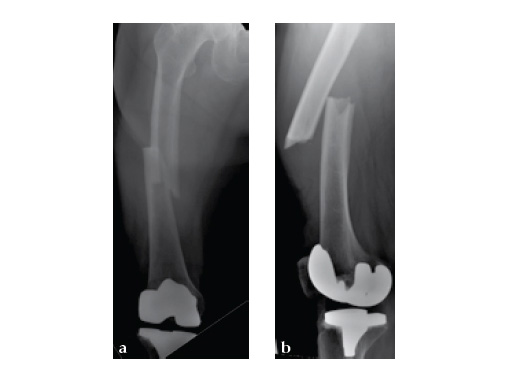

Three weeks prior to her last admission, she complains of recurrent right thigh pain for which epidural analgesics were administered for presumed radiculopathy, however preliminary x-rays and even MRI of the thigh were also taken in view of her primary complaint regarding her right thigh. These investigations did not indicate the possibility of impending bisphosphonate related femur fracture. It is clear from the radiographs that she has an obvious anterolateral bow of her femur and a thickened lateral cortex in the lateral midshaft cortical bone, which may indicate a stress fracture (see Fig 3a-b).

No edema indicated a stress fracture (see Fig 4a-b).

Based on the negative MRI thigh and positive MRI lumbar spine of multiple levels of spinal stenosis, the patient underwent epidural analgesic injection. Patient sustained right femur midshaft periprosthetic fracture the next day after her epidural injection with no trauma.

Notice the fracture decrease the emphasis on the anterolateral bow of the femur (See Fig 5a-b).